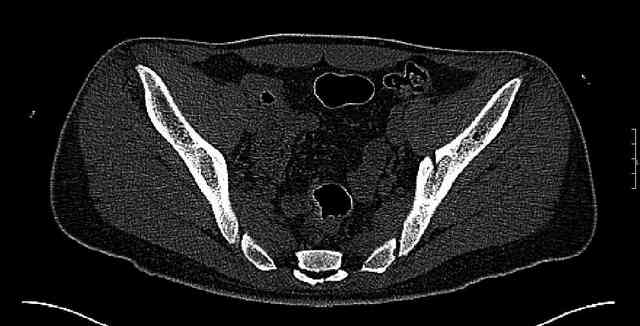

The last two images from the 3-D CT scan certainly makes the fracture look worse than the plan radiographs.

While not claiming to have the best 3D brain around, it appears to me from the limited images available, that the caudal segment is stable from the symphysis to the SI joint on the fracture side. I would love to see the rest of the transverse CT images to see where the fracture line actually exits posteriorly on both the inner and outer tables of the ilium. In my hands,

assuming that the femoral head has followed the cephalad (dome) fragment, I would use an ilioinguinal approach and take down the fracture line from anterior to posterior, distracting with a lamina spreader, if necessary, to clean out and inspect the joint. I would then reduce the cephalad fragment to the caudal fragment using jungbluth or farabeuf clamp and screws and then apply a plate and screws. If the fracture exits posteriorly would you then favor an additional posterior approach to clean out and reduce from that side?

Some more images. Does it help to guess which part of the acetabulum is displaced?

Normal appearing SI joints and a healed posterior column limb... my bet's on caudal segment displacement.